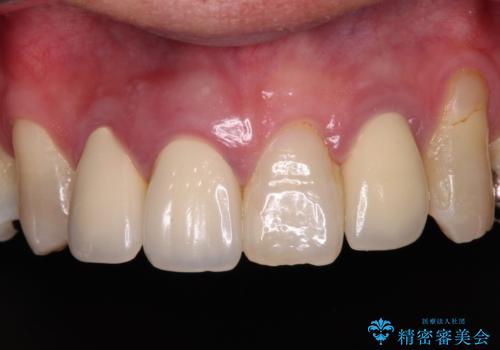

[ 乳歯の残存 ] 前歯のインプラント治療